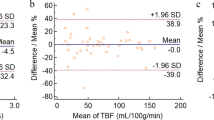

Figure 4 summarizes the diagnostic performance of the parameters. In differentiating MTs from PAs, the AUC for the combination of TBFall and ADCall (0.950; 95% CI, 0.892–1.000, p < 0.001) was higher than those for TBFall alone (0.850; 95% CI, 0.739–0.961, p < 0.001) and ADCall alone (0.885; 95% CI, 0.787–0.984, p < 0.001), which suggests that the diagnostic performance improved from medium to high with the combination of TBFall and ADCall. In differentiating MTs from WTs, the AUC for the combination of TBFall and ADCall (0.905; 95% CI, 0.805–1.000, p < 0.001) was higher than those for TBFall alone (0.855; 95% CI, 0.733–0.977, p < 0.001) and ADCall alone (0.814; 95% CI, 0.664–0.964, p = 0.002), which suggests that the diagnostic performance improved from medium to high with the combination of TBFall and ADCall. In differentiating PAs from WTs, the AUC for the combination of TBFall and ADCall (1.000; 95% CI, 1.000–1.000, p < 0.001) was higher than that for TBFall alone (0.968; 95% CI, 0.929–1.000, p < 0.001) and the same as that for ADCall alone (1.000; 95% CI, 1.000–1.000, p < 0.001), which suggested a medium diagnostic performance for TBFall alone and high performance for both ADCall alone and the combination of TBFall and ADCall. In differentiating MTs from benign tumors (BTs), including PAs and WTs, the AUC for the combination of TBFall and ADCall (0.930; 95% CI, 0.865–0.995, p < 0.001) was higher than those for TBFall alone (0.811; 95% CI, 0.709–0.914, p < 0.001) and ADC alone (0.895; 95% CI, 0.821–0.970, p < 0.001), which suggests that the diagnostic performance improved from medium to high with the combination of TBFall and ADCall.

ROC curve analyses for differentiating malignant tumors (MT) from pleomorphic adenomas (PA) (a), for differentiating MT from Warthin’s tumors (WT) (b), for differentiating PA from WT (c), and for differentiating MT from benign tumors (BT), including PA and WT (d). (a) The areas under the curve (AUCs) for all tumor blood flow parameters (TBFall) and all apparent diffusion coefficients (ADCall) indicate medium diagnostic performances for both (AUC = 0.850 and 0.885, respectively). Conversely, the AUC for the combination of the TBFall and ADCall indicates high diagnostic performance (AUC = 0.950). (b) The AUCs for the TBFall and ADCall indicate medium diagnostic performances for both (AUC = 0.855 and 0.814, respectively), whereas the AUC for the combination of TBFall and ADCall indicates high diagnostic performance (AUC = 0.905). (c) The AUCs of the TBFall, ADCall, and combination of TBFall and ADCall all indicate high diagnostic performances (AUC = 0.968, 1.000, and 1.000, respectively). (d) The AUCs for the TBFall and ADCall indicate medium diagnostic performances for both (AUC = 0.811 and 0.895, respectively), whereas the AUC for the combination of TBFall and ADCall indicates high diagnostic performance (AUC = 0.930).